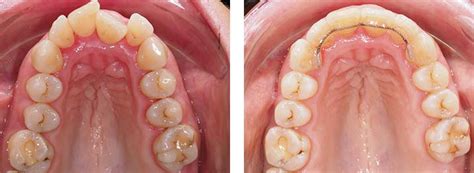

Dientes inclinados hacia dentro

Los dientes inclinados hacia dentro son una preocupación común para muchas personas, ya que afecta tanto la estética como a la salud bucodental. Uno de los factores que pueden llevar a que los dientes tengan una angulación hacia dentro es el desarrollo anormal de los dientes durante la infancia y la adolescencia. Este proceso puede deberse a la genética, donde la herencia de ciertos rasgos dentales puede predisponer a la maloclusión. La pérdida temprana de dientes de leche sin una adecuada secuencia de erupción de los dientes permanentes puede contribuir al desalineamiento dental. La succión del pulgar, el uso prolongado del chupete o incluso el hábito de respirar por la boca pueden influir en el desarrollo de dientes inclinados hacia dentro.

Tener los dientes inclinados hacia dentro es un signo de maloclusión, lo que nos indica que es un caso en el que se necesita ortodoncia para poder corregirlo. El tratamiento ortodóncico convencional con brackets metálicos o cerámicos es una opción efectiva para corregir dientes inclinados hacia dentro. La ortodoncia invisible, como el uso de alineadores transparentes, se ha vuelto cada vez más popular. Estos dispositivos personalizados ofrecen una alternativa discreta y cómoda para alinear la sonrisa. Después de completar un tratamiento de ortodoncia, es fundamental el uso de retenedores para mantener los resultados a largo plazo.

Corregir la angulación y posición de los dientes es fundamental para equilibrar la funcionalidad de la dentadura. Tener una maloclusión dental durante años nos lleva a morder irregularmente, causando daños en las piezas dentales.